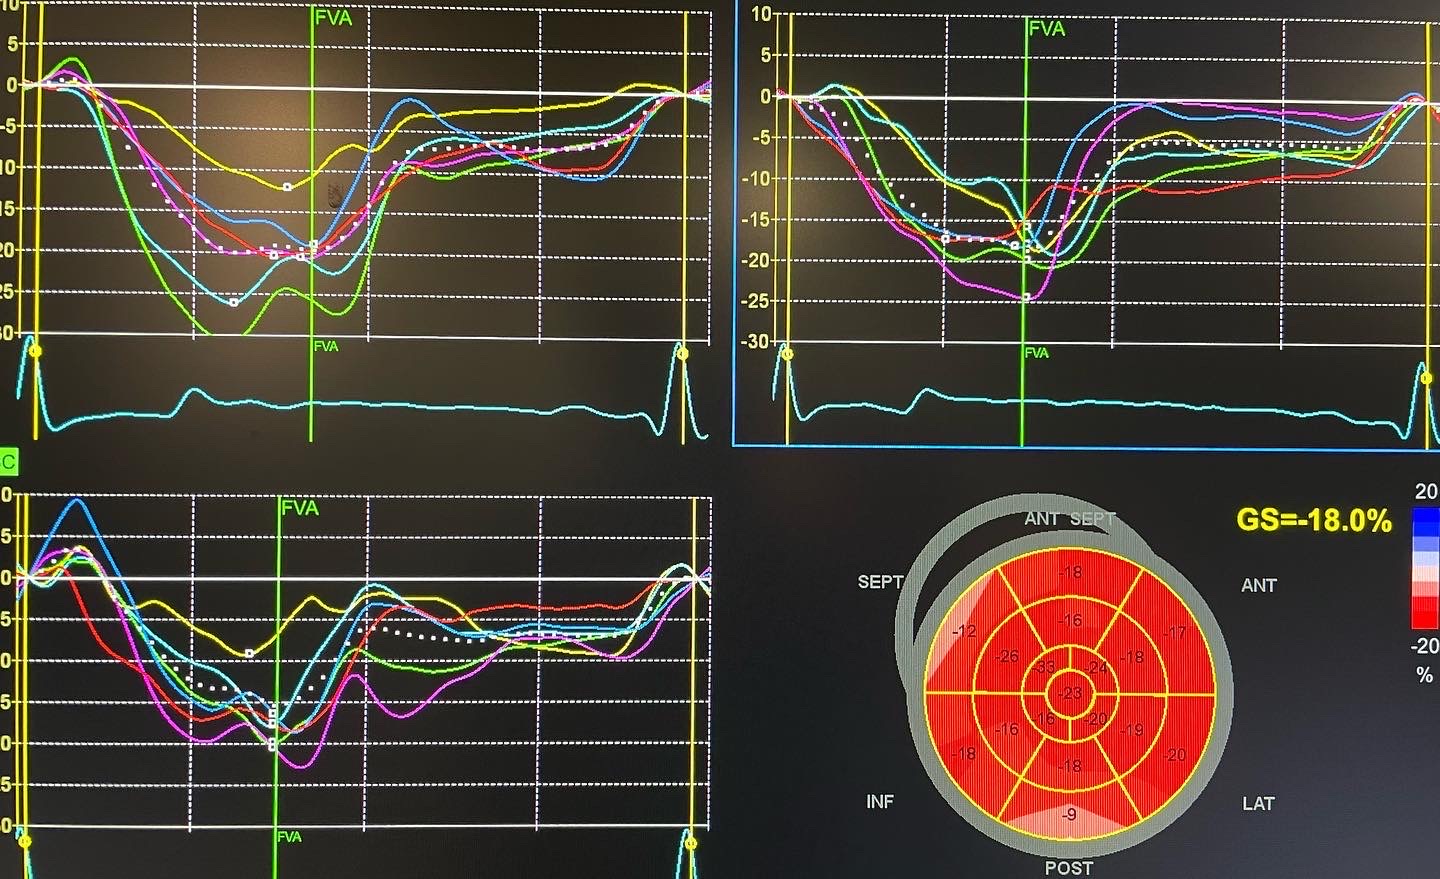

Le doppler tissulaire

Le doppler tissulaire myocardique permet de mesurer les vitesses de déplacement des différentes parties du muscle cardiaque lui-même, et non plus du sang. Le doppler tissulaire myocardique permet d’étudier les maladies du myocarde, sa viabilité, la contractilité de chaque segment, les infarctus, le synchronisme des contractions…

Très peu de centres de cardiologie possèdent cette fonctionnalité. Elle est intégrée à notre échographe de cardiologie de dernière génération : le Vivid E95 de General Electric.

Déroulé de l’examen :

Il est réalisé concomitamment à une échographie cardiaque si la fonction myocardique doit être examinée plus en finesse.